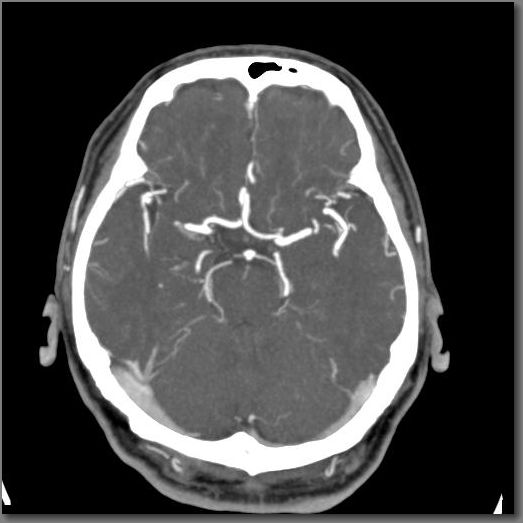

頭部CT

《頭部単純》 《頭部造影》

3D

《頭部動脈瘤》 《頭部末梢血管の動脈瘤》